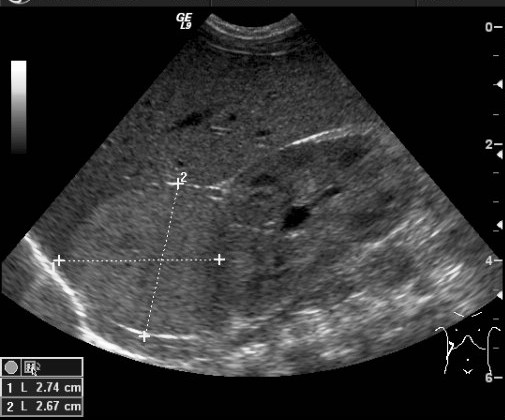

Wilms tumor. It is the most common kidney tumor in childhood that appears between 2-5 years of age. It is usually only noted when the tumor is palpable as an abdominal mass. Hematuria, hypertension, vomiting and abdominal pain are also part of the clinical picture. US examination is a basic method in both the diagnostics and the follow-up of the tumor. The tumor is normally seen as a homogenous or an inhomogeneous mass, dislocating the pyelon and the surrounding retroperitoneal blood vessels. It is important to rule out any lesion in the other kidney. MRI examination: gives a picture of the entire abdomen, kidneys included. Nodal metastases, tumor thrombus are well depictable. CT-examination: is to be chosen if MRI is not available. The tumor shows an inhomogeneous contrast enhancement and pulmonary metastases (invisible to x-ray examination) are also depictable.

27. A solid, echogenic mass arising from the right kidney. Wilms tumor. Abdominal US.